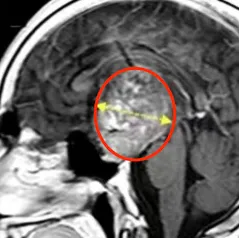

随后的12年间,患儿肿瘤持续复发并进展,至16岁时,肿瘤体积已达68.1 mm³,深度44.4 mm。这一巨大占位导致患者出现全垂体功能减退和严重左侧视力障碍,近乎失明。面对不断加重的病情,患者决定不再忍耐,毅然选择再次手术治疗。

术前情况:MRI显示鞍区与丘脑存在巨大肿瘤,归类为Bcentral病变的复发性毛细胞星形细胞瘤,侵犯左侧海马旁回及侧脑室上部。肿瘤体积68.1 mm³,深度44.4 mm,侧面角21.9°。